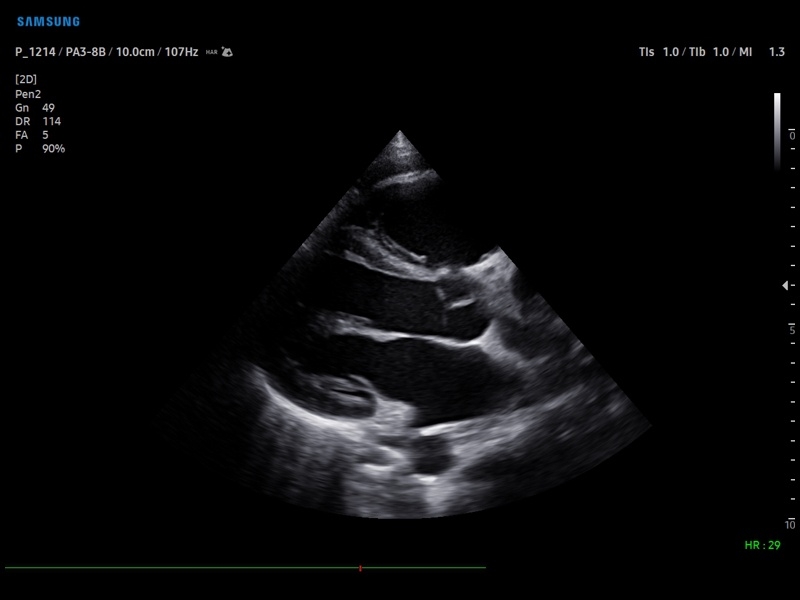

• M - одномерный режим для исследования сердца, анатомический М-режим (необходим кардиопакет), CM - цветной М-режим (необходим кардиопакет).

• Пакет кардиологических исследований.

М-режим:измерение диаметра аорты, передне-заднего размера ЛП, толщины МЖП (систолическая и диастолическая), толщины ЗСЛЖ (систолическая и диастолическая), размеров ЛЖ и ПЖ (систолический и диастолический), ФВ (Teichholz).

B-режим:измерение диаметра аорты (восходящей, дуги, нисходящей, на уровне синусов Вальсальвы, на уровне створок аортального клапана), определение размеров ЛП и ПП (максимальный, минимальный, систолический, диастолический, переднее-задний, верхнее-нижний, медиально-латеральный), расчет объемов ЛП и ПП, объемов ЛЖ (метод "Площадь-Длина", метод дисков (Simpson)), массы миокарда ЛЖ, индекса массы миокарда ЛЖ.